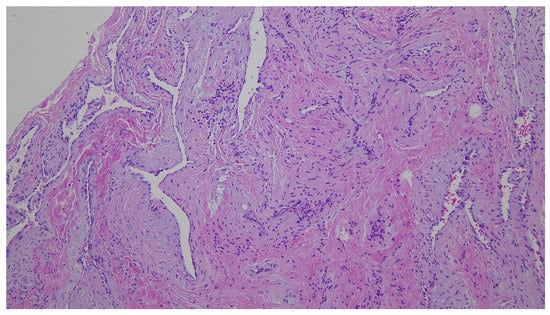

Figure 3. In surgery, the soft cystic mass was dissected from the overlying skin. It did not extend to the conchal cartilage and was completely removed. On histopathology, irregularly dilated venous channels with sparse smooth muscle cells without arteries were observed (hematoxylin-eosin, ×100). Thus, venous malformation was diagnosed. Six months after surgery, the wound had healed well and there was no recurrence.

The major difference between a vascular tumor such as hemangioma and a vascular malformation is that there is increased endothelial cell turnover on histopathology in hemangioma [2,7]. Vascular malformations rarely regress [6,9], and are associated with infection, trauma, ligation, attempted excision, and changes in serum hormone levels [5].